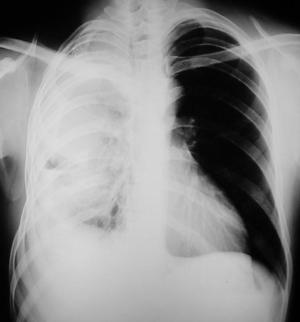

• Radiología del Tórax

Rx. Tórax PA. al momento de su Ingreso. radiopacidad difusa del hemitórax derecho, engrosamiento pleural severo con colapso parcial pulmonar, retracción mediastinal hacia la derecha, disminución de los espacios intercostales, borramiento de los senos costo-frénicos derechos.

Aumento compensatorio del volumen pulmonar y del hemitórax izquierdo.